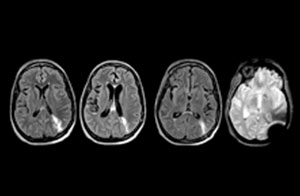

A range of protocol sheets was developed to help ensure that referring physicians order the most appropriate MRI exam. The optimized MRI protocols also include 3D contrast-enhanced imaging, allowing neurosurgeons to comfortably use the isotropic data in the operating room while performing stereotaxic surgery.

“One of the most important decisions an ED physician has to make is to admit or discharge their patient. So a physician who is better informed by an MRI exam can make this decision with more confidence. By converting to a test that has a far better potential to identify issues, physicians get a better and more certain diagnosis."

"In my experience a negative MRI, because it is so sensitive to abnormality, far exceeds the value of a negative CT. A negative MRI can allow physicians to be more confident about making discharge decisions, potentially reducing the number of admissions in cases of doubt, and offering cost savings for the institute."